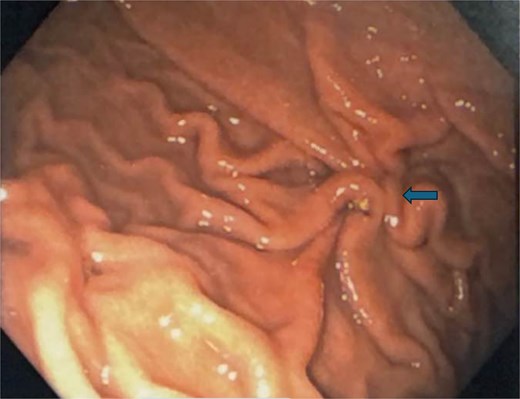

Endoscopic view of the perforation. The picture in (a) demonstrates the site of the perforation. The picture in (b) shows the use of the overstitch technique to perform the closure endoscopically. Pictures (c) and (d) demonstrate the area of perforation once the first and second layers of endoscopic closure are completed, respectively.

To aid endoscopic visualization of the small perforation, a Maryland grasper was gently inserted into it (Fig. 2); the grasper’s tip, visualized endoscopically, confirmed the exact location. The remainder of the esophagus, stomach, and duodenum appeared normal. The Overstitch™ endoscopic-suturing device, mounted on a double-channel therapeutic endoscope and utilizing a tissue-helix for full-thickness bites, was used. Three full-thickness inverted figure-of-eight 2–0 Prolene sutures were placed at the perforation. Laparoscopic visualization confirmed full-thickness suture placement before the sutures were cinched, effectively closing the gastric wall defect (Fig. 3).